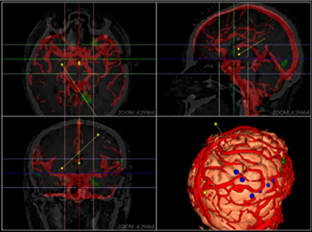

同方鼎欣専門映像製品シリーズは神経外科、整骨科、血管分析などの臨床科を?qū)澫螭摔工朐\療補助、手術(shù)計畫、分析に関するソリューションであり、醫(yī)療映像の導(dǎo)入、二次元映像閲覧、三次元再構(gòu)成、シリーズ校正融合、自動分割、自動計算、手術(shù)計畫などの機(jī)能を統(tǒng)合しています。臨床科の専門要求を満足する一方で、完璧、強(qiáng)力、信頼、便利なツールプラットフォームを提供します。

三次元ボリューム描畫再構(gòu)成(VR)、三次元面描畫再構(gòu)成(SR);

融合(Fusion)、融合結(jié)果の三次元再構(gòu)成;

3Dシリーズ血管セクションと管理;

血管中心線描畫、曲面再構(gòu)成(CPR);

神経外科手術(shù)計畫モジュール;